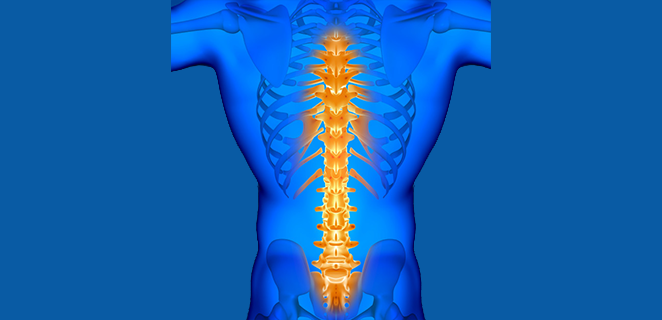

داء شيرمان

داء شويرمان هو اضطراب تطوري في العمود الفقري، ويتميز بتشوه